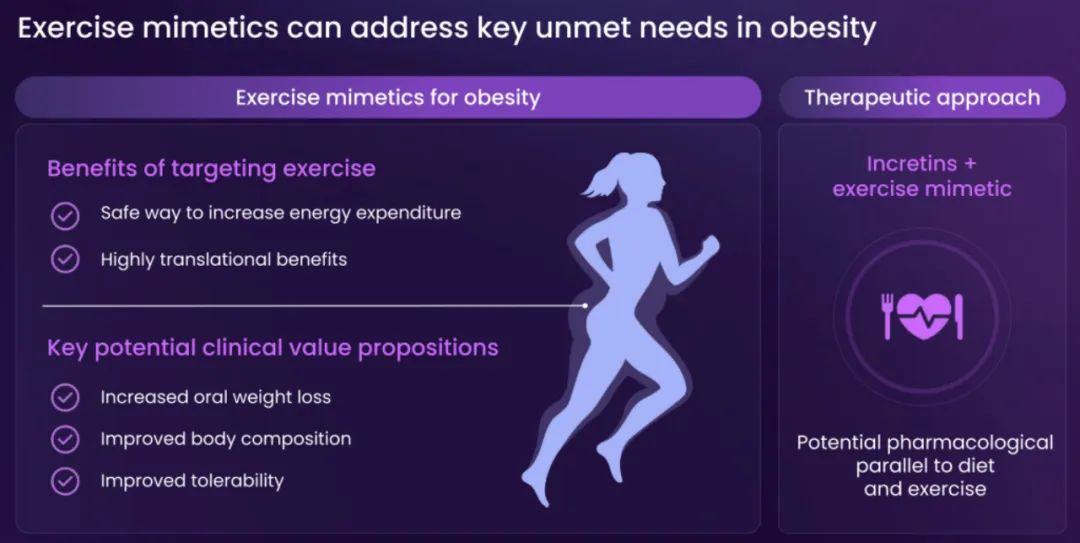

BioAge Labs是一家临床阶段的生物制药公司,致力于针对人类衰老生物学,开发肥胖等代谢疾病的治疗产品候选物。

BioAge Labs的主要关注点是代谢疾病,这是全球最大的医疗保健挑战之一。BioAge Labs的主要候选产品 Azelaprag是一种口服小分子,在8个 1 期临床试验中,265 名受试者的耐受性良好。在临床前肥胖模型中,azelaprag 显示出能够使胰高血糖素样肽-1 受体 (GLP-1R) 激动剂诱导的体重减轻增加一倍以上,同时恢复健康的身体成分并改善肌肉功能。

BioAge Labs还计划在 2025 年上半年启动一项针对阿泽拉普拉格单药治疗的胰岛素敏感性概念验证试验,以支持潜在的适应症扩展。我们还在开发口服小分子脑渗透性 NLRP3 抑制剂,用于治疗由神经炎症引起的疾病。